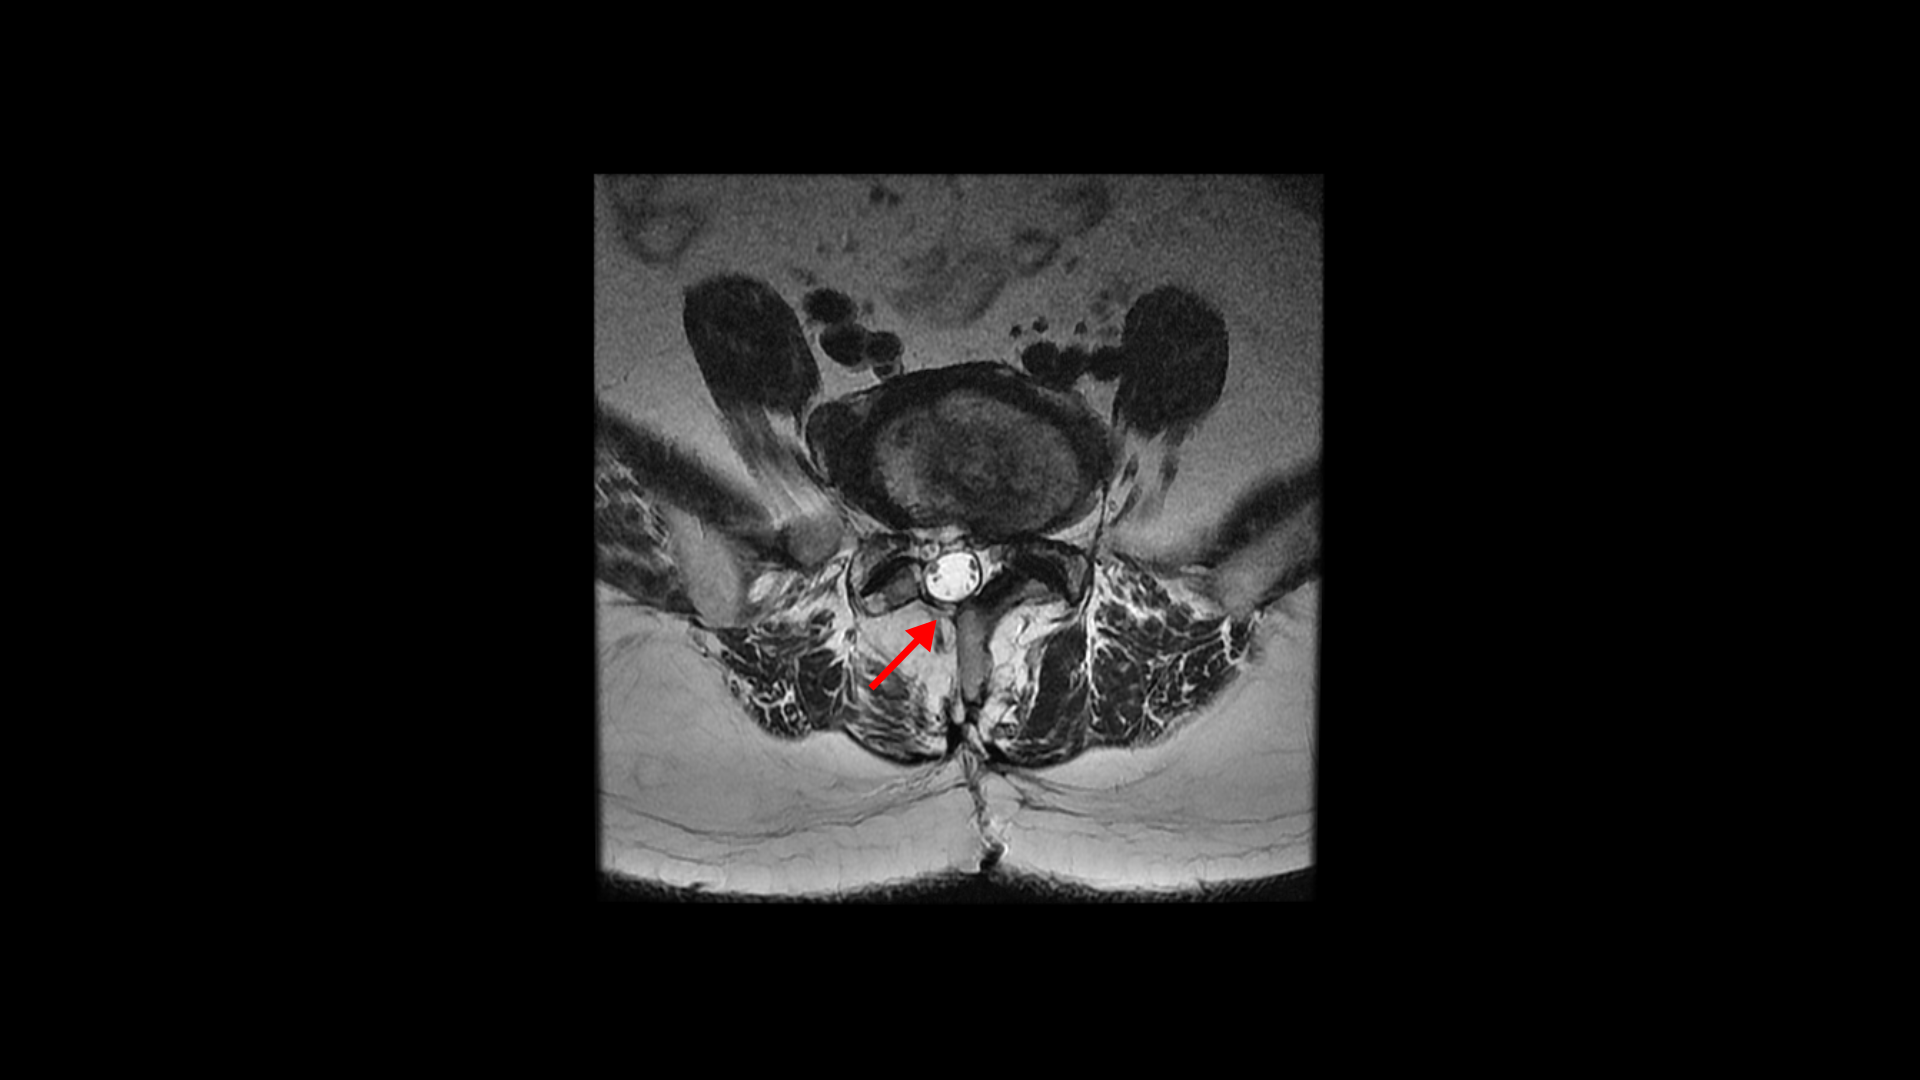

올해 초에 디스크가 4번 5번에서 또 오른쪽으로 심하게 터져서 결국은 후궁과 후관절, 황색인대를 모두 다 제거하고 나사를 박는 유합술을 하셨습니다.

그런데 유합술 후 오른쪽 다리의 증상은 좋아졌으나 상대적으로 괜찮았던 왼쪽 다리에 심한 방사통과 마비 증상이 생겼습니다. 수술 후에 집도의로부터 수술은 잘 됐으나 수술한 자리가 부어있어서 신경을 눌러서 그럴 거니까. 1년 이상 기다리면 좋아질 것이라는 얘기를 들었습니다. 그런데 저희 모커리한방병원은 디스크나 협착증, 전방전위증 등으로 오랫동안 다리 방사통을 겪은 환자분들 중 수술받은 분들께 수술 후 남아있거나 새로 생기는 방사통이나 마비 증상은 회복을 위해 1년씩 혹은 그 이상 오래 기다릴 필요가 없다고 말씀 드리고 있습니다. 보통은 수술집도의 분들의 설명은 수술 전에 오래 눌려있던 신경이 다시 회복되는데 시간이 오래 걸리기 때문에 기다려야 한다고 얘기하는데, 저희 관점에서는 척추 수술 후 회복되는데 시간이 오래 걸리는 이유가 전혀 다릅니다.